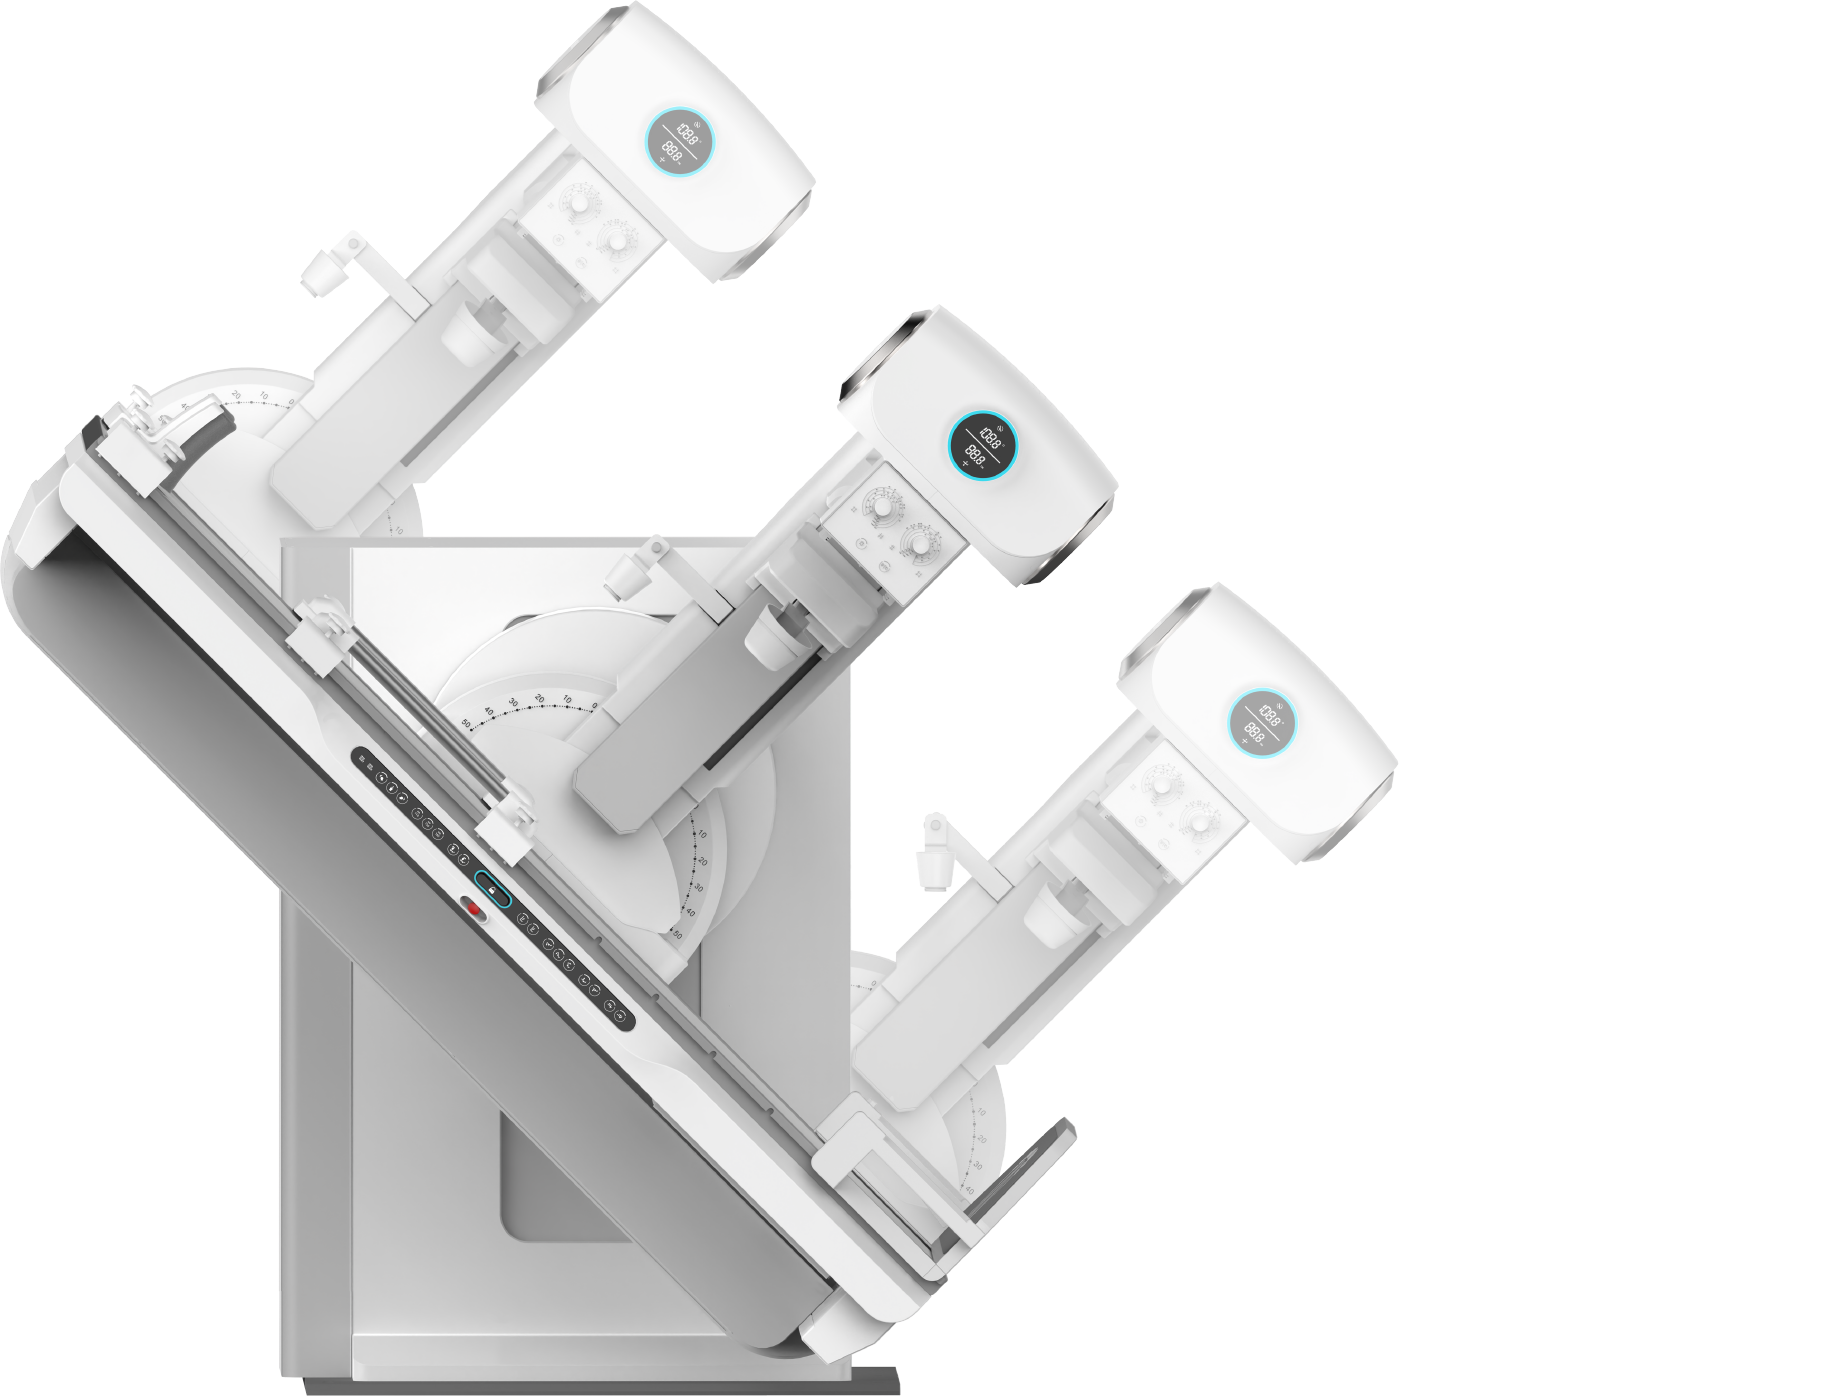

研创驾驶舱式多维一体化胃肠诊断系统,贴近临床深度创新,让复杂操控一手掌控,让全场景功能一机兼容,不断提升医患的使用体验

诊断床-45°倾斜, 满足逆行造影需求(45床)

多维诊断床,45cm升降覆盖,方便患者检查

1800mm SID电动变焦,满足胸片拍摄

管球立柱±45° 满足DR倾斜斜位摄影

1450mm大行程运动,满足全身影像链覆盖